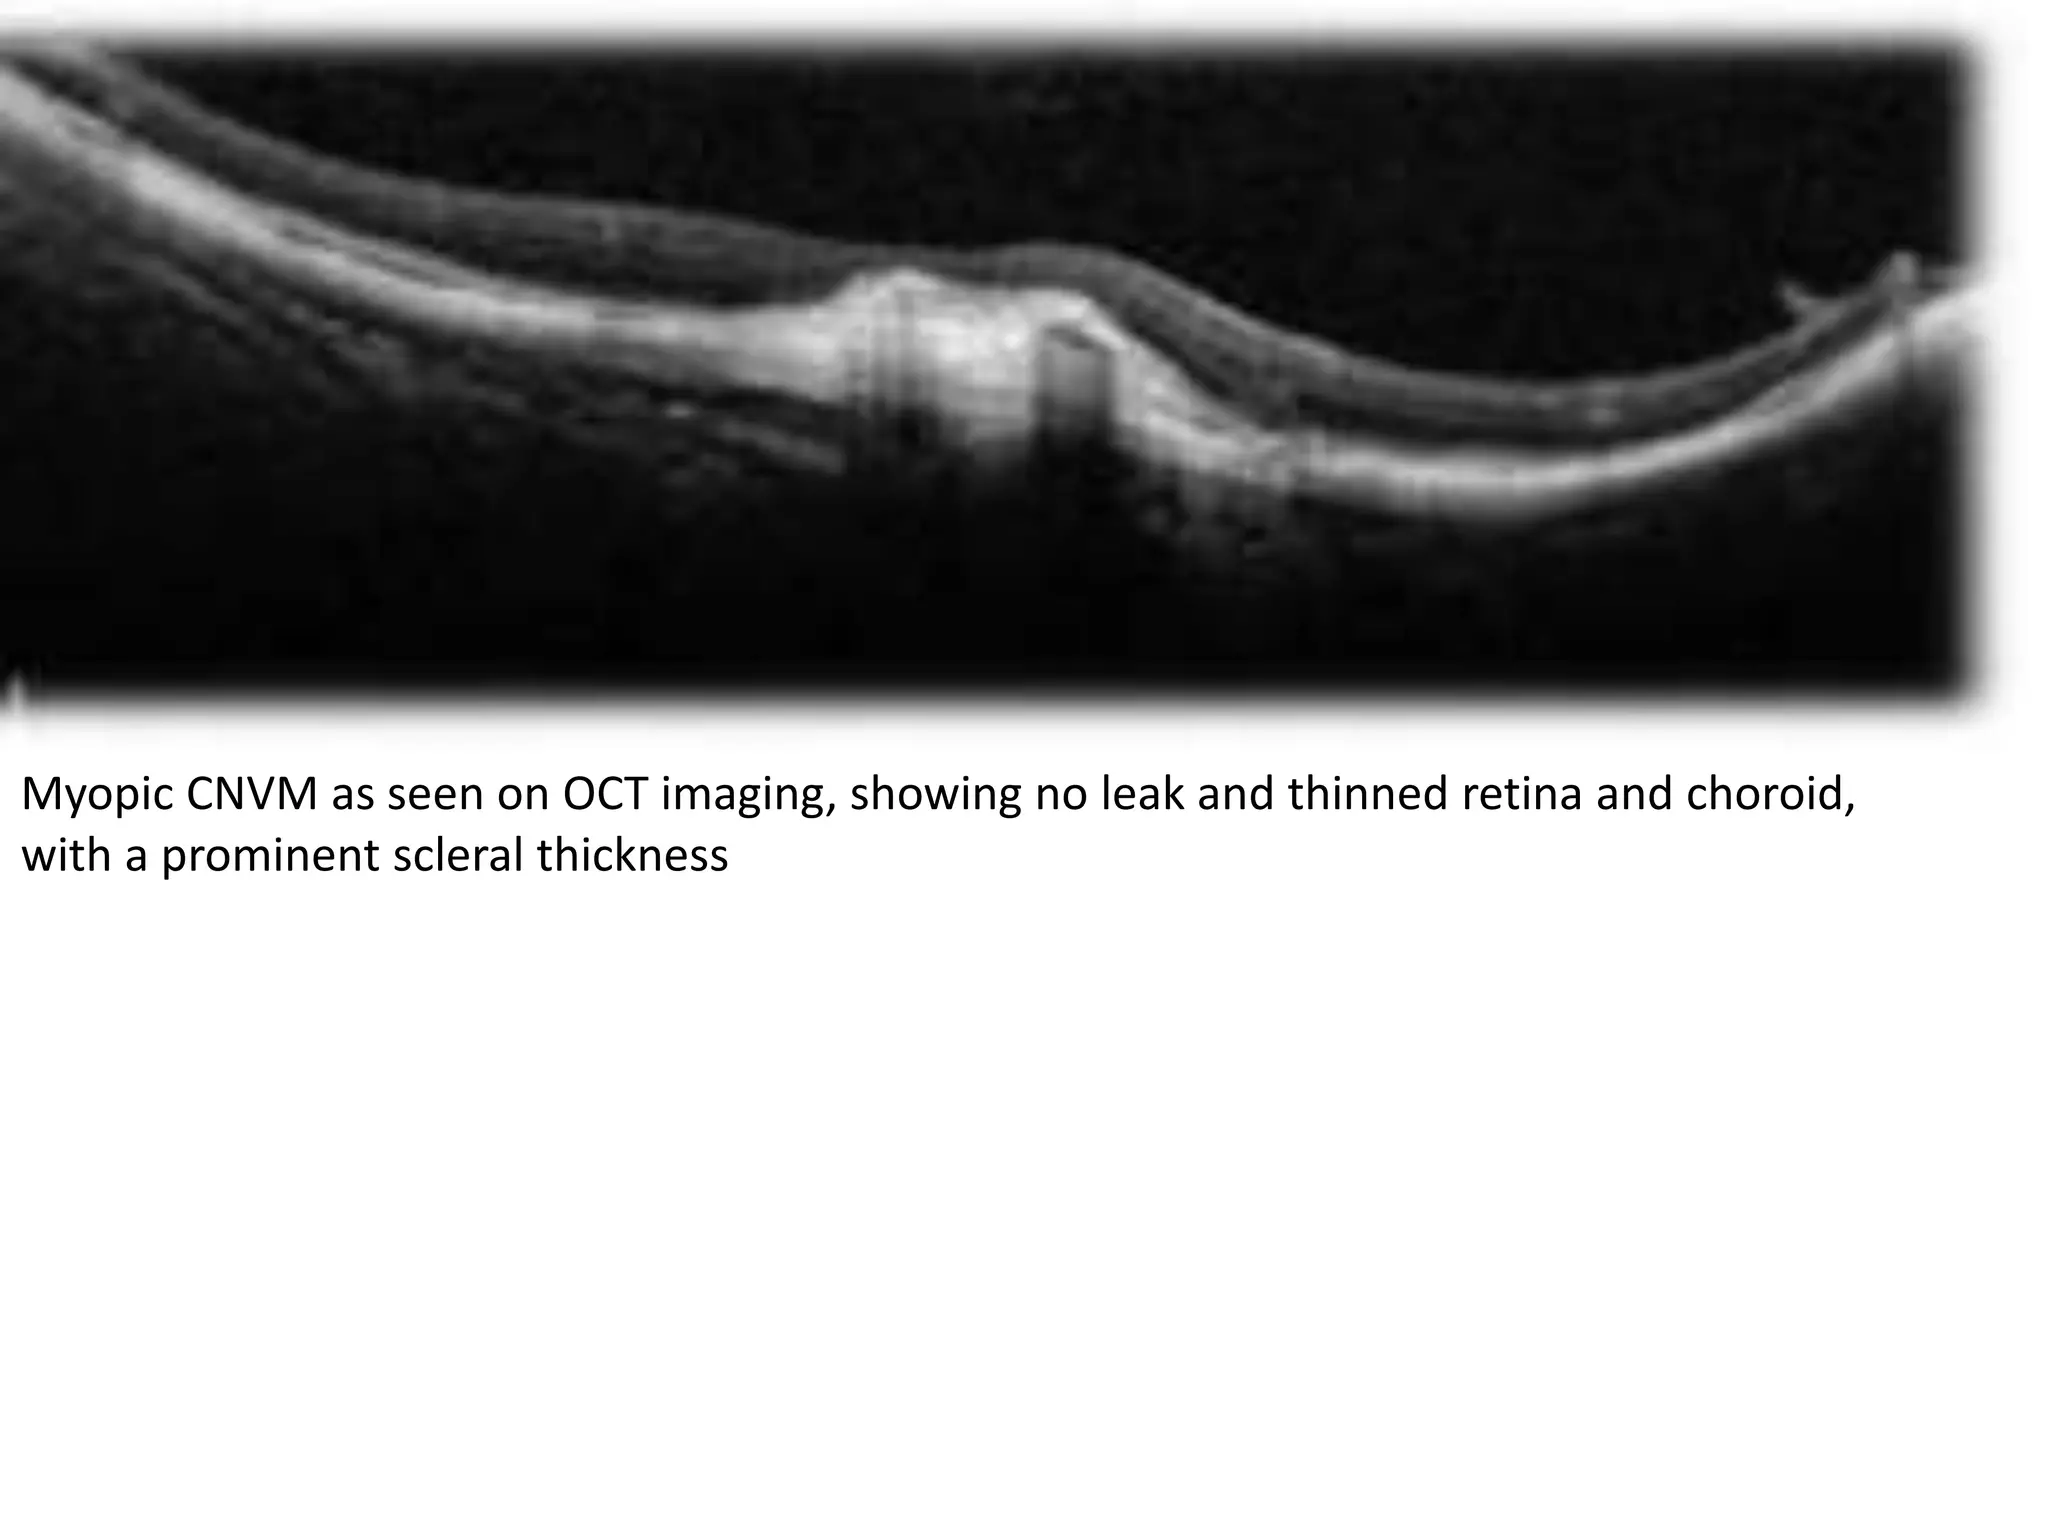

Myopic CNVM as seen on OCT imaging, showing no leak and thinned retina and choroid,

with a prominent scleral thickness

Myopic CNVM asseen on OCT imaging, showing no leak and thinned retina and choroid, with a prominent scleral thickness